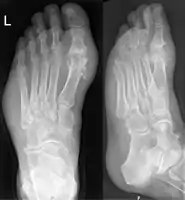

Gout may be diagnosed and treated without further investigations in someone with hyperuricemia and the classic acute arthritis of the base of the great toe (known as podagra). Synovial fluid analysis should be done if the diagnosis is in doubt.[18][51] Plain X-rays are usually normal and are not useful for confirming a diagnosis of early gout.[7] They may show signs of chronic gout such as bone erosion.[47]

Gout on X-rays of a left foot in the metatarsal-phalangeal joint of the big toe. Note also the soft tissue swelling at the lateral border of the foot.